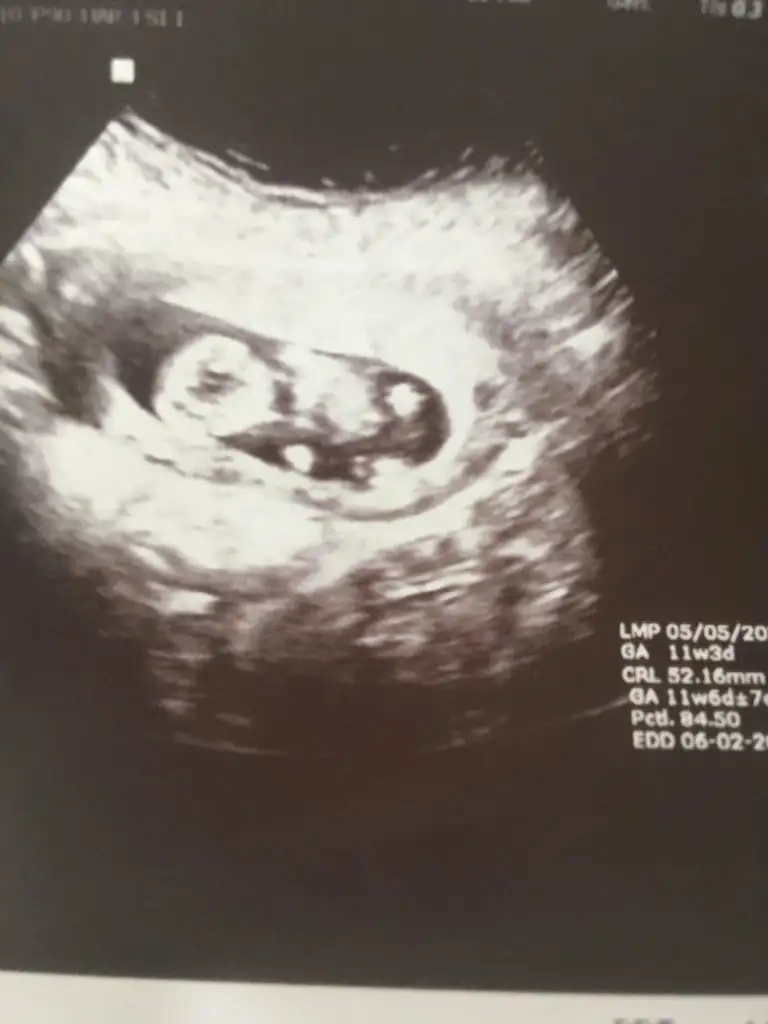

Kız gibi sanki emin olamadımEki Görüntüle 2892053 Eki Görüntüle 2892054 @Ikra meyra acaba müsait olunca bakar mısın? 11+6 oldu belli olur mu biraz?

Teşekkür ederimKız gibi sanki emin olamadım

Bugün cinsiyetini öğrendik,kızımız olacak. Teşekkürler zaman ayırdığınız için.Erkek gibi sanki

Sağlıkla gelsin prensesBugün cinsiyetini öğrendik,kızımız olacak. Teşekkürler zaman ayırdığınız için.